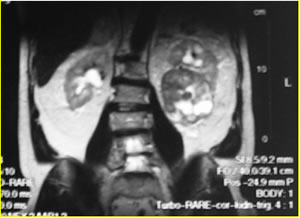

МРТ

таза

ДИАГНОЗ

Осн-й: ДГПЖ.

Осл-я: Хроническая неполная задержка мочи.

Гидронефроз един. правой почки. ХПН II A ст. Хроническая

инфекция мочевой системы. Множественные камни мочевого

пузыря